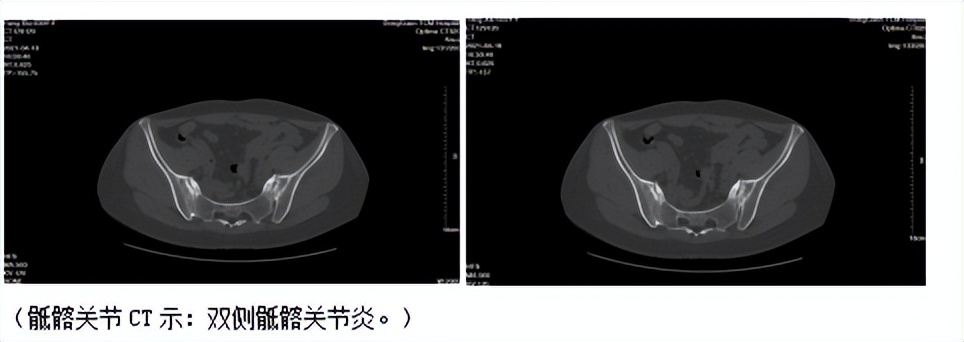

(CT显示)